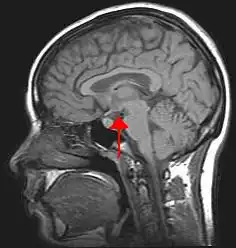

Hypothalamus

Hypothalamus (původní český název je podhrbolí, slovensky se někdy nazývá podlôžko) je částí mezimozku (diencephalon). Jeho činnost spočívá hlavně ve slaďování jednotlivých vnitřních orgánů do komplexní odpovědi. Například připravuje všechny orgánové soustavy na zvýšenou fyzickou nebo psychickou zátěž.

Hypothalamus vytváří přední stěnu a dno III. mozkové komory. Od thalamu ho odděluje sulcus hypothalamicus. V hypothalamu bylo popsáno 22 jader. Klasickou klasifikací se stalo dělení podle Le Gros-Clarka, kterým se řídí i členění podle Nomina Anatomica (1977).